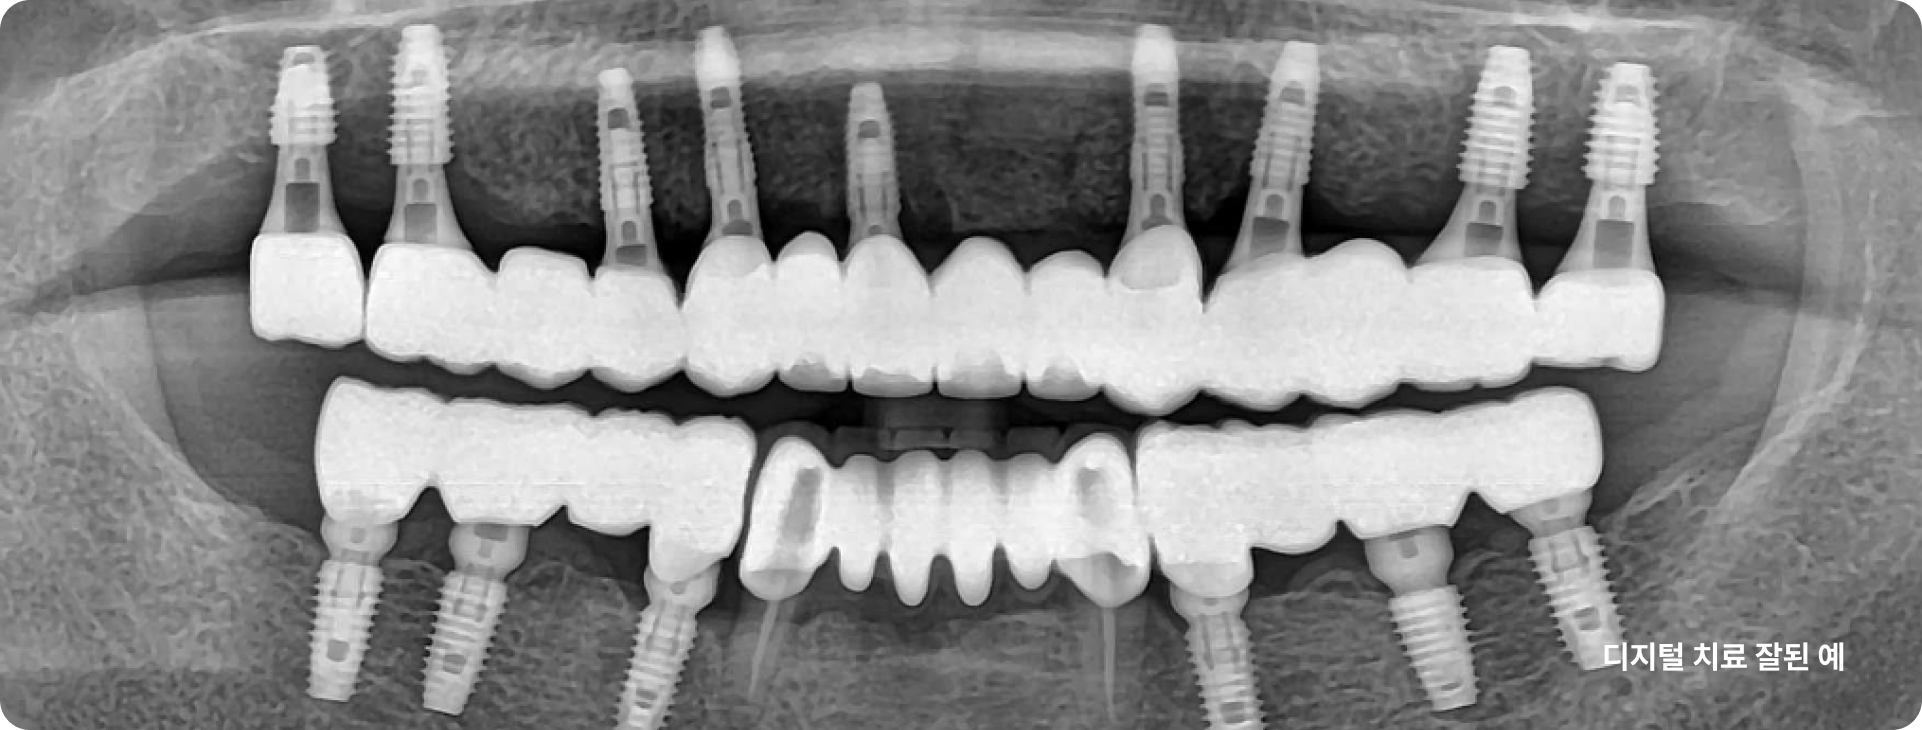

많은 치과의사들이 보철 중심으로 계획된 임플란트 시술의 중요성을 인정합니다.

그리고 이 과정에서 디지털 치과로의 전환이 필요함을 인정합니다.

이제는 임플란트 회사, 임플란트 브랜드 선택의 관점에서 벗어나서 임플란트 수술 진단부터 최종 치아 제작까지. 이 모든 과정에서 보철학적 목표를 디지털 방식으로 어떻게 완성해 내는지가 선택의 관점이 되어야 합니다.

이로운 치과는 간단하고 정확하며 안전한 치료를 위한 디지털 진료 방식을 지향합니다.

이로운 치과는 디지털 진료를 통해 정확한 임플란트 식립 위치를 파악하여

아날로그 치료에서 발생할 수 있는 문제를 예방합니다.

이로운치과의 디지털 임플란트 과정

1

implant

CT

2

Oral Scanner

3

3Shape Implant Studio

4

3D Printer

5

15년 노하우의

디지털 가이드 임플란트 수술

6

7

Custom Abutment Design and Milling

8

Zirconia Crown Design and Milling, Sintering

모든 과정은 이로운치과의 의료진과 디지털 치과기공 전문인 와이앤씨 기공소 와의 긴밀한 커뮤니케이션 하에 협업하여 진행합니다.